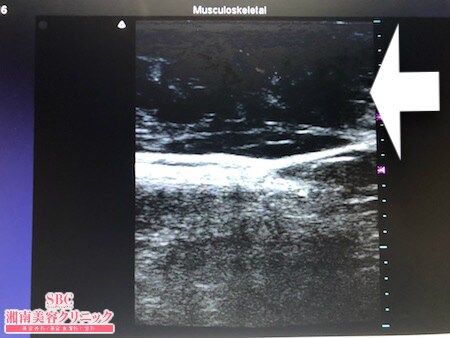

No.226929【脂肪吸引】【動画あり】湘南美容外科脂肪吸引最高責任者である竹田先生による脂肪吸引のフォトギャラリー!タイトなお洋服を着ると皮下脂肪が乗っかるのが嫌なので脂肪吸引をします!術中3Dタッチビュー・左腰